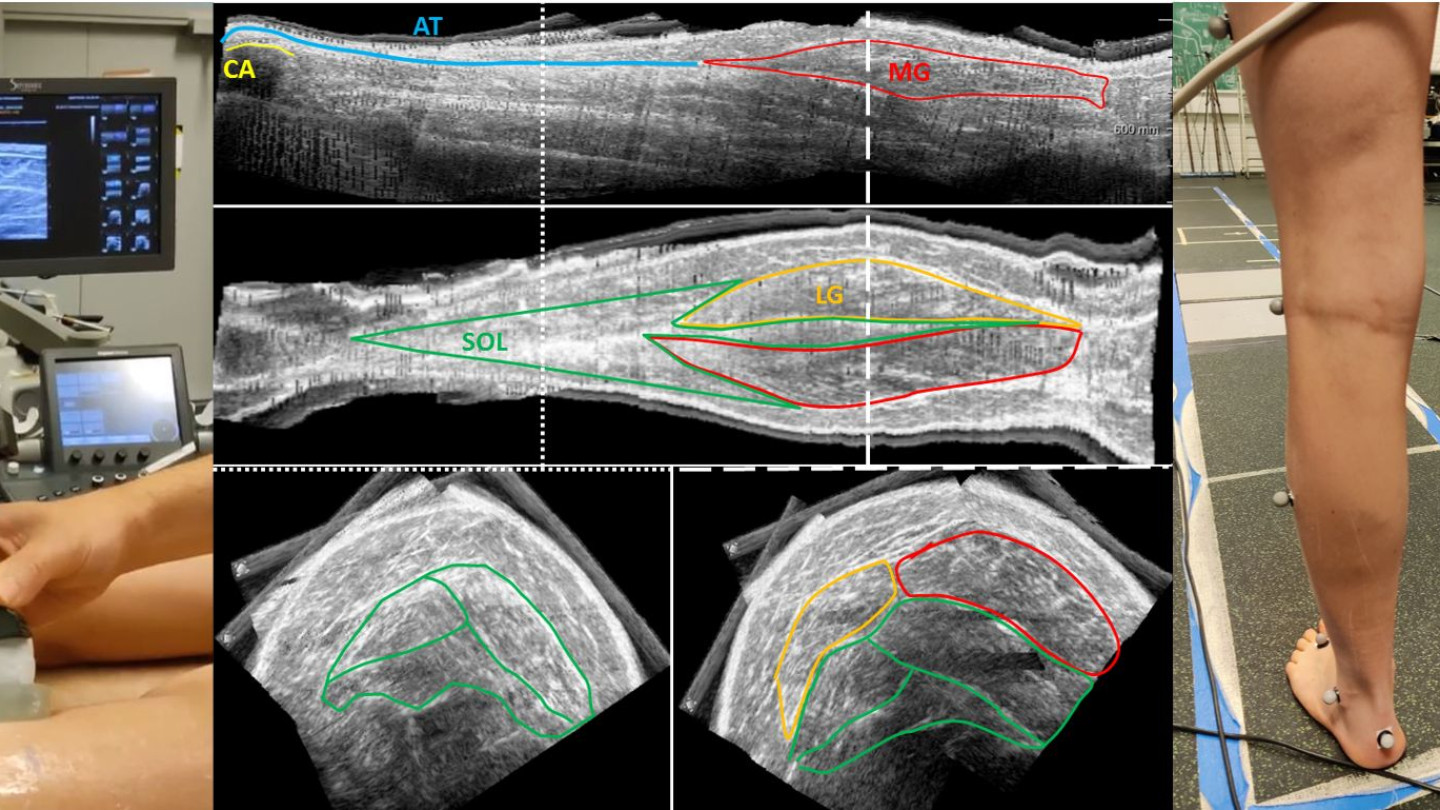

Ankle resistance is also related to the changes in musculoskeletal properties. These changes occur in muscle composition, with fatty infiltration and an increase in the accumulation of connective and fibrous tissues which replace the contractile elements, impeding the muscle to contract functionally. In addition, muscle morphology is altered, including reduced muscle volume and length compared to age-matched typically developing children. Their combination contributes to muscle contractures, increased stiffness (rigidity), and reduced muscle strength. Current methods for analysing morphology, composition, and stiffness are based on magnetic resonance imaging (MRI). MRI technique can be reliably used for estimating intramuscular content. However, an ultrasound (US) approach would be crucial for frequent clinical applications (ideally for monitoring treatments) since it allows low costs and frequent usage. Yet, US methodologies are not yet well established for extracting these parameters. Once the musculoskeletal technique is established, the 3D US framework will be used in JYU for extracting muscle volume, length, and echo-intensity. Children will also participate in 3D gait analysis with simultaneous 2D US imaging. The US probe will be positioned over the medial gastrocnemius (MG) muscle-tendon junction, and over the MG belly allowing imaging of MG and soleus. Since the final goal in cerebral palsy is to improve gait ability, musculoskeletal properties were recently analysed also during walking. However, the relationship between passive and active musculoskeletal properties is still unclear. This relationship will show how altered passive and active musculoskeletal properties affect gait.